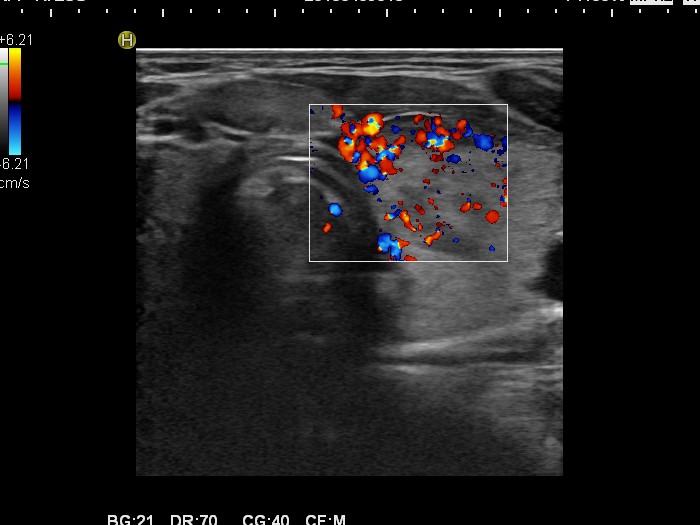

Follow-up investigation 30 months after first visit (ultrasonographic picture 6)

Patient one year after discontinuation of thyrostatics in hyperthyroid state

Left lobe, transverse scan, color Doppler mode. The vascularization is increased.